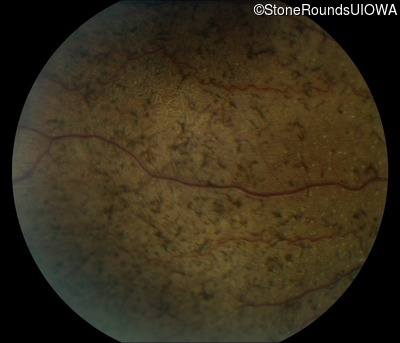

Fundus Photography - Right - 10/300

Exemplar